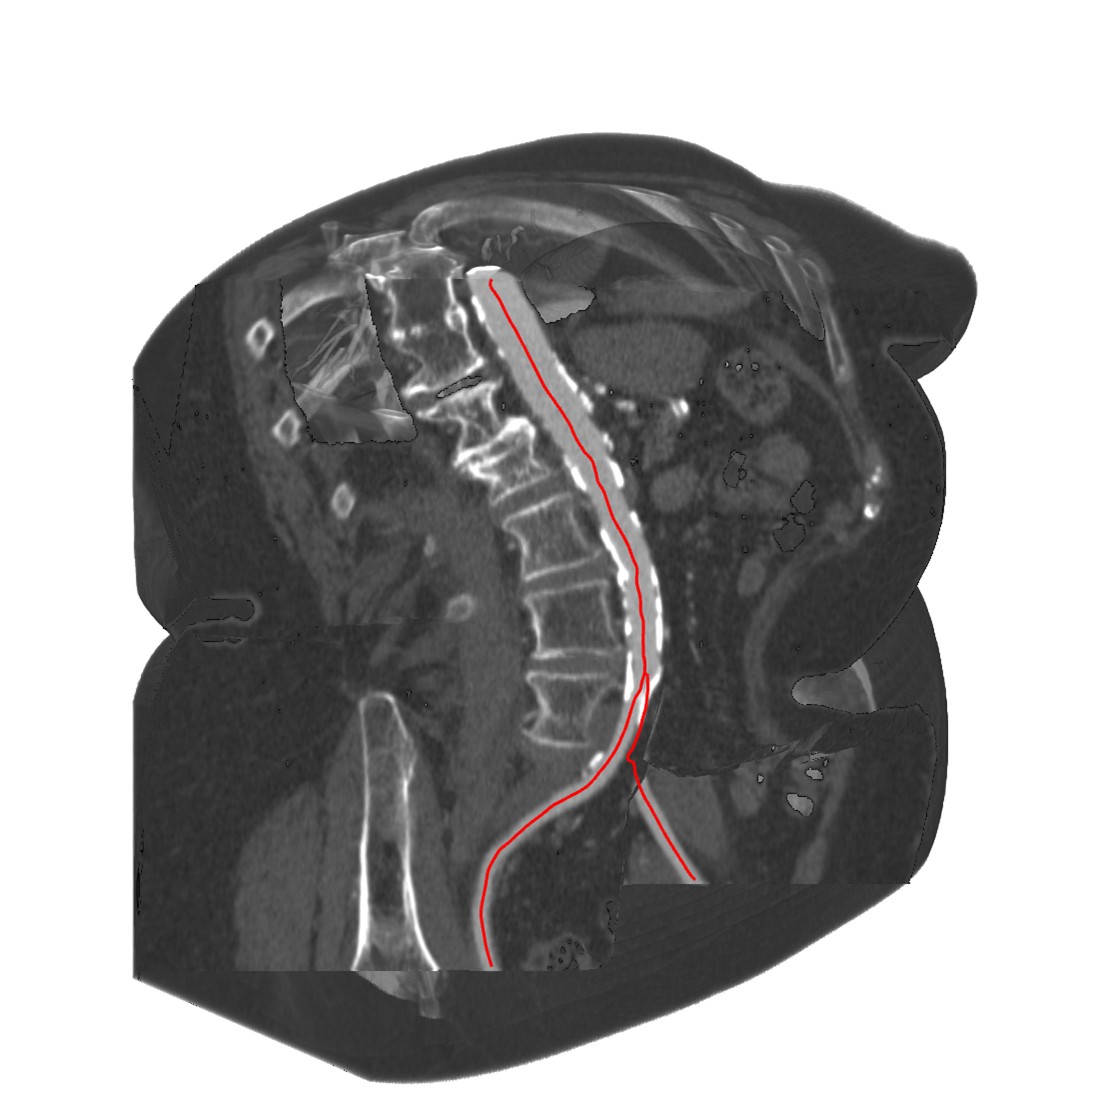

@article{Auzinger2013,

title = {Vessel Visualization using Curved Surface Reformation},

author = {Thomas Auzinger and Gabriel Mistelbauer and Ivan Baclija and Rüdiger Schernthaner and Arnold Kochl and Michael Wimmer and M. Eduard Gröller and Stefan Bruckner},

url = {https://www.cg.tuwien.ac.at/research/publications/2013/Auzinger_Mistelbauer_2013_CSR/, Project Page},

doi = {10.1109/TVCG.2013.215},

issn = {1077-2626},

year = {2013},

date = {2013-12-01},

journal = {Visualization and Computer Graphics, IEEE Transactions on},

volume = {19},

number = {12},

pages = {2858-2867},

abstract = {Visualizations of vascular structures are frequently used in radiological investigations to detect and analyze vascular diseases. Obstructions of the blood flow through a vessel are one of the main interests of physicians, and several methods have been proposed to aid the visual assessment of calcifications on vessel walls. Curved Planar Reformation (CPR) is a wide-spread method that is designed for peripheral arteries which exhibit one dominant direction. To analyze the lumen of arbitrarily oriented vessels, Centerline Reformation (CR) has been proposed. Both methods project the vascular structures into 2D image space in order to reconstruct the vessel lumen. In this paper, we propose Curved Surface Reformation (CSR), a technique that computes the vessel lumen fully in 3D. This offers high-quality interactive visualizations of vessel lumina and does not suffer from problems of earlier methods such as ambiguous visibility cues or premature discretization of centerline data. Our method maintains exact visibility information until the final query of the 3D lumina data. We also present feedback from several domain experts.},

note = {* TA and GM: Joint First Authors. Presented at SciVis 2013.},